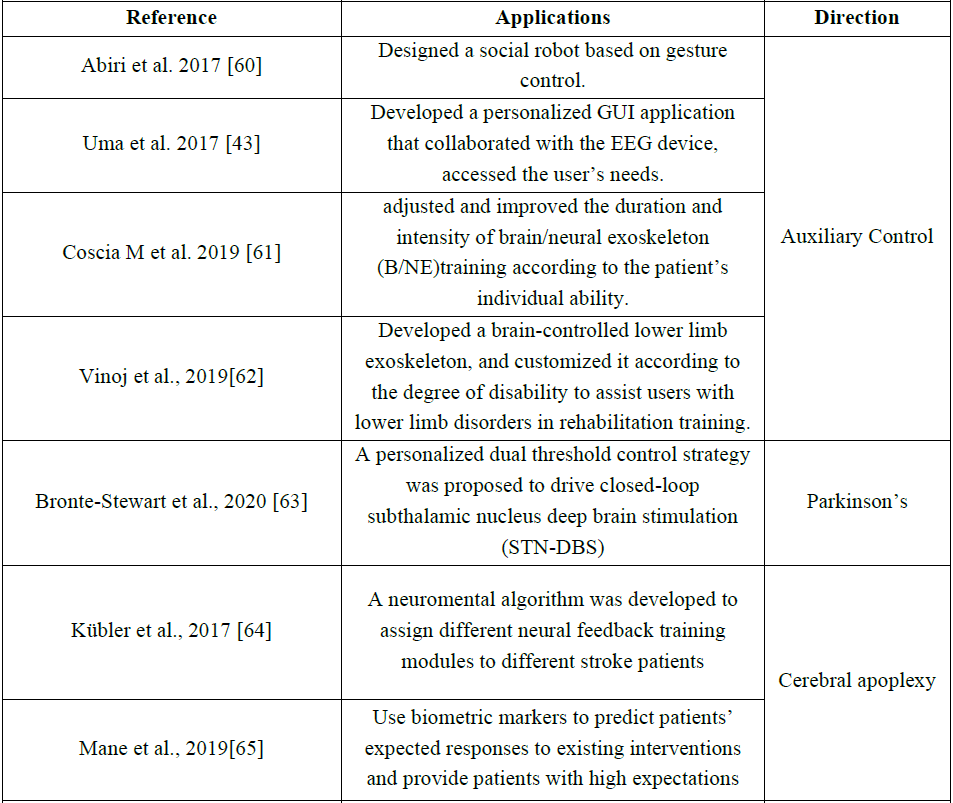

4 个性化BCI应用

不管是实验范式的个性化、脑信号处理的个性化还是神经反馈的个性化,其最终目的都是搭建BCI系统平台并投入到实际的应用中。在这个部分中,我们将探讨个性化BCI在运动功能障碍康复、精神疾病治疗康复、情绪识别等领域的应用。表3中列出了迄今为止主要的个性化BCI应用,同时本章将对表中内容进行评述。

Table 3 Different applications of personalized BCI

4.1 个性化BCI在辅助控制中的应用

目前BCI在辅助控制方面应用最多。其中BCI在通信与控制、运动替代等方向已经得到了大量的研究以及较为广泛的应用。

1)通信与控制

无论是BCI的通信还是控制,其基本原理都是类似的,都是通过识别特定模式的大脑信号,实现对外部指令/符号的输出。通过 BCI,严重残疾的用户可以与其他人进行交流,并对外部环境进行控制。Abiri等设计了一个基于手势控制的社交机器人[60],通过与神经反馈机制相结合,为用户定制解码模型以控制社交机器人的手势。Uma,M等开发的了一个个性化的GUI应用程序与EEG设备协作以满足用户的需求[43]。Abiri等证实,在光标控制中,个体的可视化能力与其光标的可控性水平之间存在正相关关系,这可以为个性化的光标控制提供方向[70]。

2)运动替代

AnnalisaColucci等在2022年发表的文献中提到[71],将大脑/神经活动转换为可穿戴执行器的控制信号,能够让大脑/神经外骨骼(B/NE)在运动功能受损的情况下执行运动。在个性化BCI中,Coscia M等[61]通过监测预测精神疲惫的生理生物标志物,例如心率变异性、皮肤电反应或呼吸频率,根据患者的个体能力进行调整改善B/NE的控制参数。此外,Vinoj等人开发了可以根据残疾程度进行个性化定制[62]下肢外骨骼(brain-controlled lower limb exoskeleton BCLLE)。

4.2 个性化BCI在神经疾病康复中的应用

下面以帕金森(Parkinson disease, PD)和脑卒中后的治疗康复为例,讨论个性化BCI在运动与认知功能障碍康复领域的应用。

1)帕金森病的治疗康复

目前还没有能完全治愈帕金森病的方法[72],个性化BCI有望使帕金森病患者的症状有所好转。Bronte-Stewart H M等利用双向深部脑机接口(bidirectional deep brain-computer interface ,dBCI)提出了个性化双阈值控制策略,并将该策略应用于神经或运动输入,以驱动闭环丘脑底核深部脑刺激 (subthalamic nucleus - deep brain stimulation STN-DBS ),用于治疗帕金森病[63]。这是一种个性化的BCI,与传统BCI不同,其根据特定用户的活动状态和用药周期无缝地调整神经刺激的参数,目的是为特定的帕金森病患者提供治疗康复效果最佳的参数,该研究首次证明了闭环深部脑刺激(Deep brain stimulation ,DBS)对PD可行性和有效性。

2)脑卒中后康复

脑卒中会导致患者认知障碍或/和运动障碍[73],针对这两种障碍的康复,当前个性化BCI主要利用基于BCI的神经反馈训练以及经颅电刺激(transcranial electrical stimulation TES)进行干预。

(1)认知障碍康复

研究发现增加特定EEG频带的能量可以改善认知表现,Kübler A等利用该发现设计了基于BCI的神经反馈训练模块以增强脑卒中患者的认知功能,提出了一种神经心理学算法,根据神经心理测试结果,可以为特定脑卒中患者定制或分配不同的、最适合的神经反馈训练模块[64]。

(2)运动障碍康复

Mane R等采用经颅直流电刺激结合BCI(transcranial Direct Current Stimulation coupled BCI TDCS-BCI)对脑卒中患者上肢运动障碍进行干预,发现脑对称指标和功率比指标(Power ratio index PRI)是TDCS-BCI干预的最佳预测指标,这些预测指标有助于识别不同患者的生物特征标志[65]。可以利用特定患者的这种生物特征标志预测其对现有干预措施的预期反应,将预期收益最高的干预措施推荐给患者,从而实现个性化的康复方案。与传统BCI相比,这种个性化BCI应用解决了通用方案对不同患者的适应性问题,为每个患者提供适合自己的、预期收益更高的康复方案。

4.2 个性化BCI在精神障碍康复中的应用

以从大脑向外输出指令为主的BCI(输出式BCI)其功能主要实现与外部世界的通信与控制,与这类BCI相比,还有另一类 BCI,主要由外部设备或机器绕过外周神经或肌肉系统直接向大脑输入电(如DBS),经颅直流/交流电刺激(Transcranial direct/ alternating current stimulation,tDCS/tACS[74-76]))、磁(如经颅磁刺激(Transcranial Magnetic Stimulation,TMS))、声(如经颅超声刺激(Transcranial ultrasound stimulation,TUS))和光等刺激或神经反馈,以调节中枢神经活动,这类BCI可用于精神障碍的物理干预以促进康复。

输入式BCI对精神障碍的调节功效一个主要因素是对特定患者优化最佳神经调节或刺激参数,即个性化的刺激参数设置。Fellous, J.-M.等采用先进的机器学习算法识别大脑状态,并利用神经特征优化刺激参数,他们引入了可解释的人工智能(ExplainableArtifificial Intelligence XAI),以数据驱动的方式识别特定的生物特征标志(如事件相关电位(Event-related Potentials,ERPs)[76-79])来检测异常神经活动[80]。例如,在酒精成瘾患者和动物模型中观察到延迟和/或降低的ERP振幅[78,79,81,82]。当检测到异常的神经活动时开启对大脑的刺激,自适应调整刺激参数,并在大脑活动正常化后立即关闭刺激[66]。ERPs和机器学习可以支持精神症状的诊断,并对特定受试者的疾病进展和治疗结果进行预测,从而实现个性化的治疗康复[67,83]。

4.3 个性化BCI在情绪识别中的应用

情绪调节对个体的身心健康很重要,情绪识别是情绪调节的基础。不同个体的情绪会随时间和环境的变化而变化[84],因此,需要为特定个体定制BCI以识别情绪。

情感BCI (Affective BCI,aBCI)通过测量神经生理信号来监测情绪状态,帮助用户主动定制心理任务,以提高人机交互的性能[68]。例如,个体利用情绪变化操控游戏,当其意识到自己的情绪状态会影响游戏参数时,他会根据自己的偏好主动改变情绪,通过操控游戏的结果和情绪反馈对心理任务进行调整,实现基于个性化的aBCI操控游戏[85]。

此外, Daly等研发了一种用于音乐脑机接口(Brain-computer music interfaces,BCMI)的情绪状态检测系统[69],其中的BCMI通过音乐诱发用户情绪以帮助其调节情绪[37]。Daly 等针对每个受试者训练分类器(实验中使用的音乐刺激由情感算法作曲(Affective algorithm composition AAC)系统创作[86,87]),实验结果表明,与普通的BCIM相比(P<0.05),个性化的BCMI系统能够更准确地检测受试者的情绪(P<0.01)。